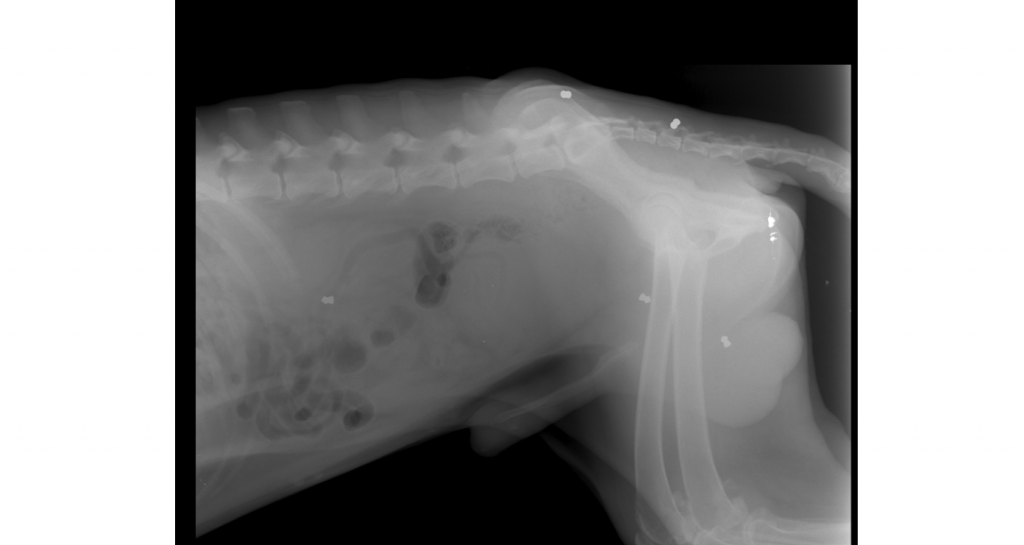

Όπως καταγράφει το trikalavoice.gr στις ακτινογραφίες που υπεβλήθη φάνηκε να φέρει ακόμη τα σκάγια τα οποία δέχθηκε, στο σώμα του (οι εφτά άσπρες κουκκίδες). Φαίνεται καθαρά και στη φωτό που αναρτούμε στο trikalavoice.gr. Όχι για να σοκάρουμε, αλλά για να συνετίσουμε και να κάνουμε αυτούς που προβαίνουν σε τέτοιες ενέργειες να αντιληφθούν το τι ακριβώς πράττουν. Ο Ροντ αναρρώνει σήμερα από τα τραύματά του, αν και η υγεία του είναι ιδιαίτερα βεβαρημένη.